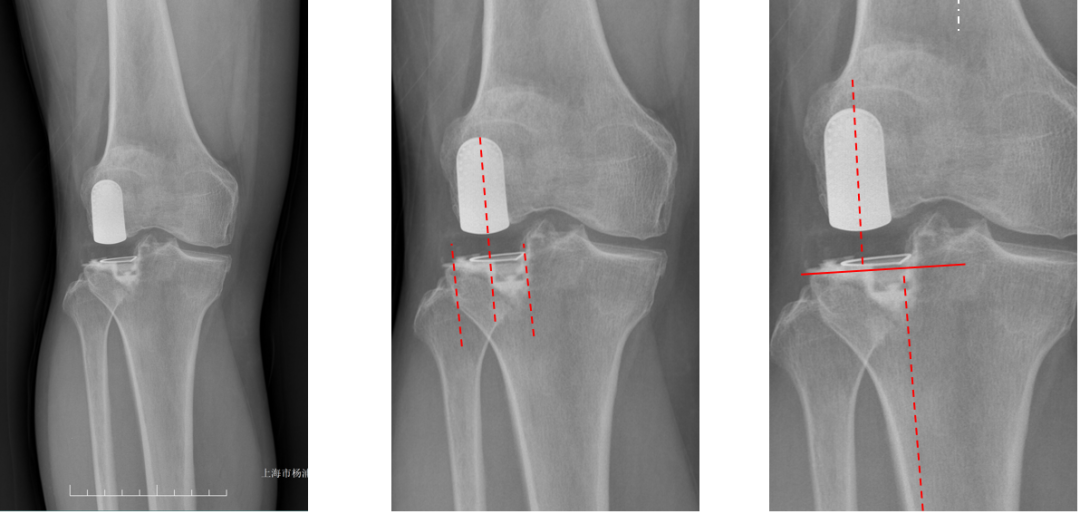

正位片标准胫骨和股骨假体位置

AP位假体位置:胫骨假体无明显内外翻,与胫骨轴线垂直,内侧缘与胫骨平台内侧缘齐平; 股骨假体长轴与胫骨假体垂直,中线一致。

胫骨假体3°内翻

AP位胫骨与股骨假体位置:胫骨假体内翻3°,股骨假体中轴线与胫骨假体垂直。

胫骨假体内侧悬挂

AP位胫骨假体位置:胫骨假体内侧悬挂>2mm。

股骨假体偏内放置

AP位胫骨与股骨假体位置:股骨假体轻度内翻,中轴线与胫骨假体中线不一致,偏内侧。